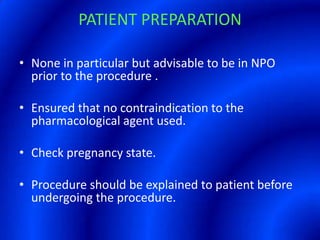

This document provides information about a barium swallow procedure. It begins with an introduction and overview of the embryology and anatomy of the pharynx and esophagus. It then describes the procedure itself, including preparation, technique, views obtained, and indications. Specific conditions that may be examined include pharyngeal and esophageal webs, foreign body impaction, scleroderma, dysphagia, mediastinal masses, and carcinoma. Diagrams are provided to illustrate normal anatomy and various pathological findings.